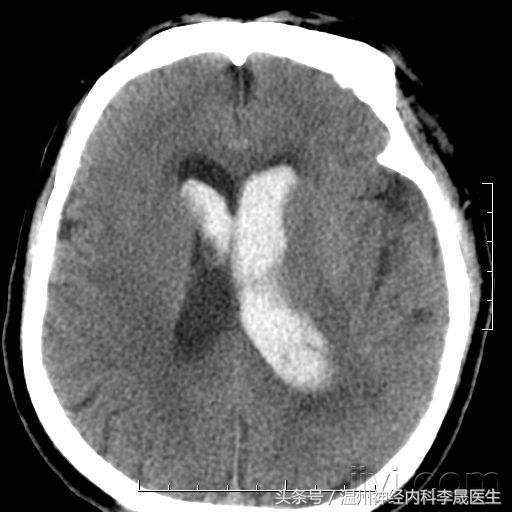

5.原发性脑室出血

少见,为脑室内脉络丛或室管膜下动脉破裂所致,占3%-5%. 其临床特征如下:

① 小量出血:多数。

头痛、呕吐,意识障碍或一过性意识障碍,脑膜刺激征及血性CSF,酷似蛛血,预后好,可完全恢复.。

② 大量出血:

突然头痛、频繁呕吐、迅速昏迷、四肢软瘫及去脑强直发作、针尖样瞳孔、眼球分离斜视或浮动等、病情危重,迅速死亡。

原发性脑室出血